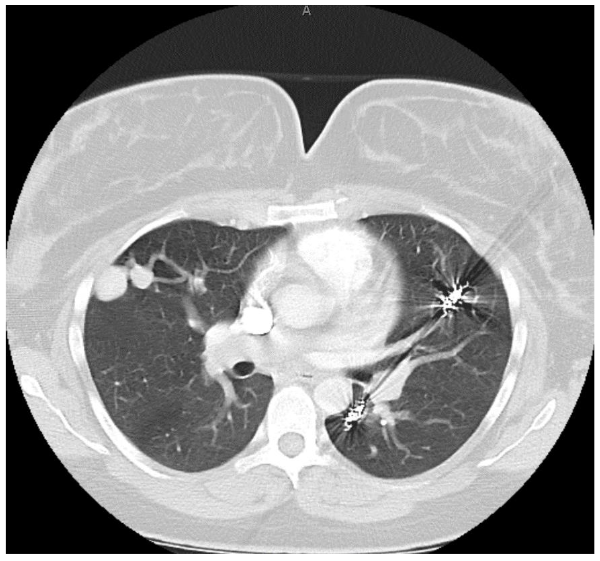

On postpartum day 1, the patient experienced an episode of acute hemoptysis, expelling blood, tachycardia, and hypotension. Pre-laboratory and imaging studies were obtained, and pulmonary, anesthesia, and high-risk obstetrics were consulted. The patient underwent a computed tomography scan which demonstrated her PAVM with the largest measuring 32mm.